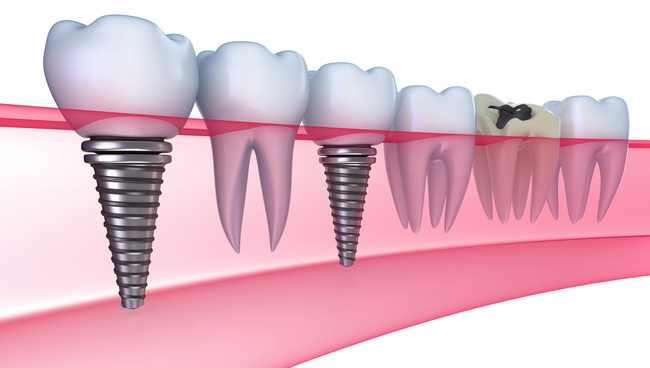

- Kada nedostaje jedan ili vise zuba

- Kada nedostaju svi bočni zubi (kutnjaci i pretkutnjaci) jednostrano ili obostrano

Nekada je standard u nadoknadi nedostajucih zuba bio zubni most. Bilo da nedostaje jedan ili više zuba, ukoliko bismo se opredelili za zubni most, morali bismo brusiti susedne zube.Međutim zbog potrebe da se brušenjem modifikuju (i donekle time potencijalno ugrožavaju) nekada potpuno zdravi susedni zubi, danas se radije preporučuje zubni implant.

Da bi se izradio zubni most neophodno je da postoji bar jedan kutnjak, distalni nosač mosta. Ukoliko nedostaju svi kutnjaci ugradnja zubnog implantata ili više njih je jedini način da se dobije fiksni rad. U protivnom bi pacijent morao da nosi protezu.

- Očuvanje prirodnih zuba - Zubi oko implantata ostaju netaknuti jer nema potrebe za brušenjem.Implanti mogu služiti kao nosači zubnih proteza,jer su one na taj način mnogo stabilnije i udobnije za nošenje. Implanti ni na koji način ne ugrožavaju kvalitet ostalih zuba, što se može desiti pri izradi zubnih mostova.